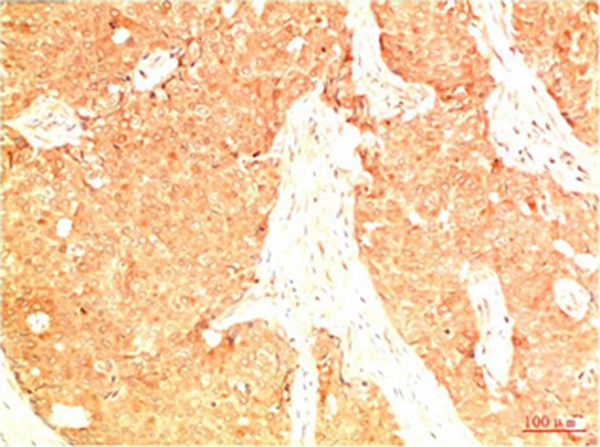

分类: 科研抗体货号: P43828别名: Cellular tumor antigen p53 (Antigen NY-CO-13) (Phosphoprotein p53) (Tumor suppressor p53)应用: IHC反应种属: Human,Mouse,Rat